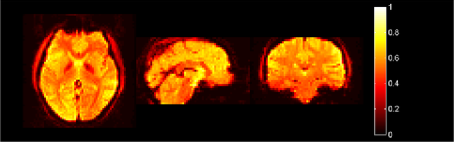

In Figure 1 an example of the connectome data can be seen. The data set is a four-dimensional volume, with three spatial dimensions and one temporal dimension. At each spatial location, there is a recording of a time series, or, more relevantly for our functional data analysis, for each time, there is a complete three-dimensional

|

| (a) |

|

| (b) |

volume present. In this paper, we will consider the spatial data as a function, and the time series to be repeated (and correlated) observations of that function. This implies that the spatial covariance function will be six-dimensional, and it is this covariance that is intrinsically of interest in resting state fMRI studies (as connectivity maps are simply approximations to this covariance). While it might be possible in individual cases to use a supercomputer to handle matrices of this order [see Long et al. (2011), e.g.], in most cases where there are large numbers of subjects to process, an approximation, or, equivalently, dimension reduction, will be needed, and this will now be the focus of the next section.

In Figure 2, a resting state fMRI data set is shown after a separable dimension reduction to 64 () dimensions was conducted, using separable projections and finding the covariance functions using (9) from the previous section. Recall that the original dimensions are

and therefore more than 2000 times as high. Indeed, the traditional way of choosing the number of components uses some threshold for the amount of variance to be explained. For the above subject (and similarly for the other subjects) 64 components explain less than 1% of the variation, which would seem to be of little use in a dimension reduction context. However, by performing a careful statistical analysis of the relationship between the type of change-points to be detected and the choice of the projection, it will be seen that in many instances, even such a small number of components will be enough.

Finally, in Figure 2 the subject shown has components which do not indicate level shifts and, in fact, the null hypothesis is not rejected for this subject, either with or without FDR correction.